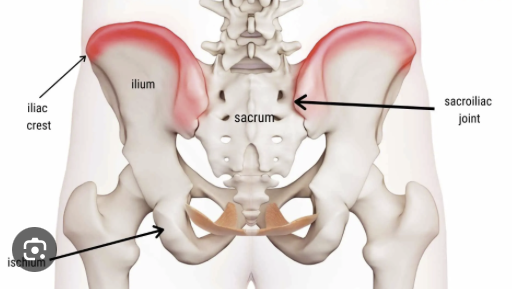

ive been cursed with shitty hips that make it look like im a fatass even while low bf%